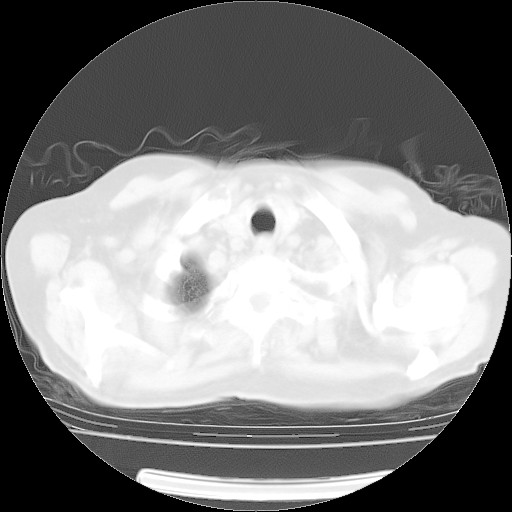

4月14日肺部CT

23.JPG

24.JPG

25.JPG

26.JPG